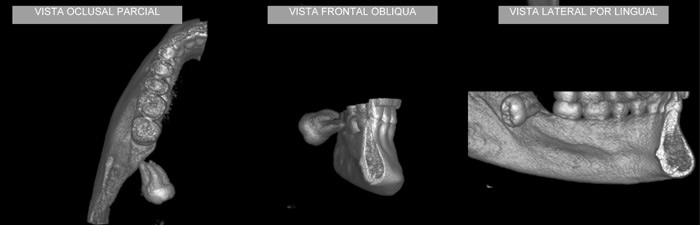

CASO 2 - Localização de dente retido

História clínica de exodontia do dente 38 há um ano, sem no entanto localizar o elemento dentário acreditando que o paciente havia engolido o dente. Na radiografia panorâmica observa-se a presença do dente 38 superposto ao ramo. Na tomografia localiza-se o dente no assoalho bucal.